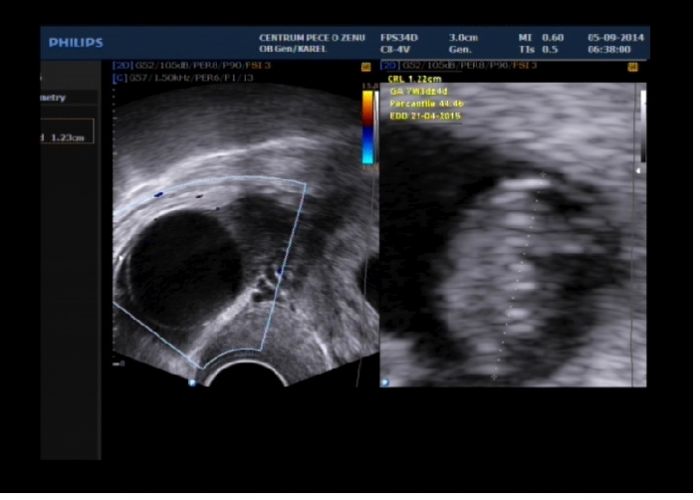

Mě fotečku z UZ poslal na e-mail, na první toho taky moc vidět není. Je to 8tt. Tak taky doufam,že na další kontrole 24.9. bude už něco k vidění. A já taky nic neplatím, ani minulé těhu jsem nic neplatila. Jen mi to poslal i s tou cystou, co mám vlevo na vaječníku.